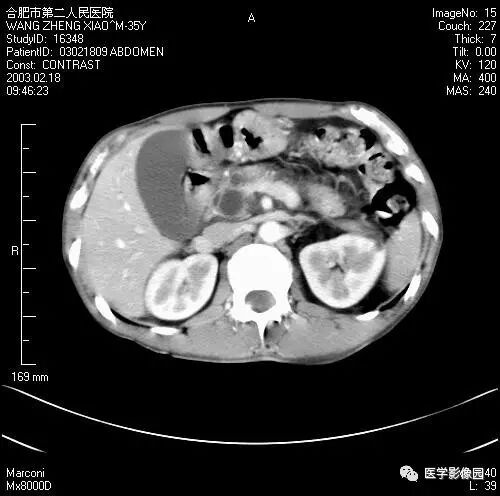

图6-4-13胰腺癌

CT平扫见胰体、尾部局限性肿大,

其内境界不清的低密度灶(↑);

肝右叶有多个低密度转移灶(长↑),

并见腹水